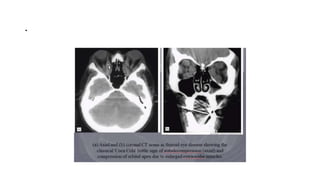

• CT scans of the orbit are essential,

should include PNS and rule out

any sinus disease.